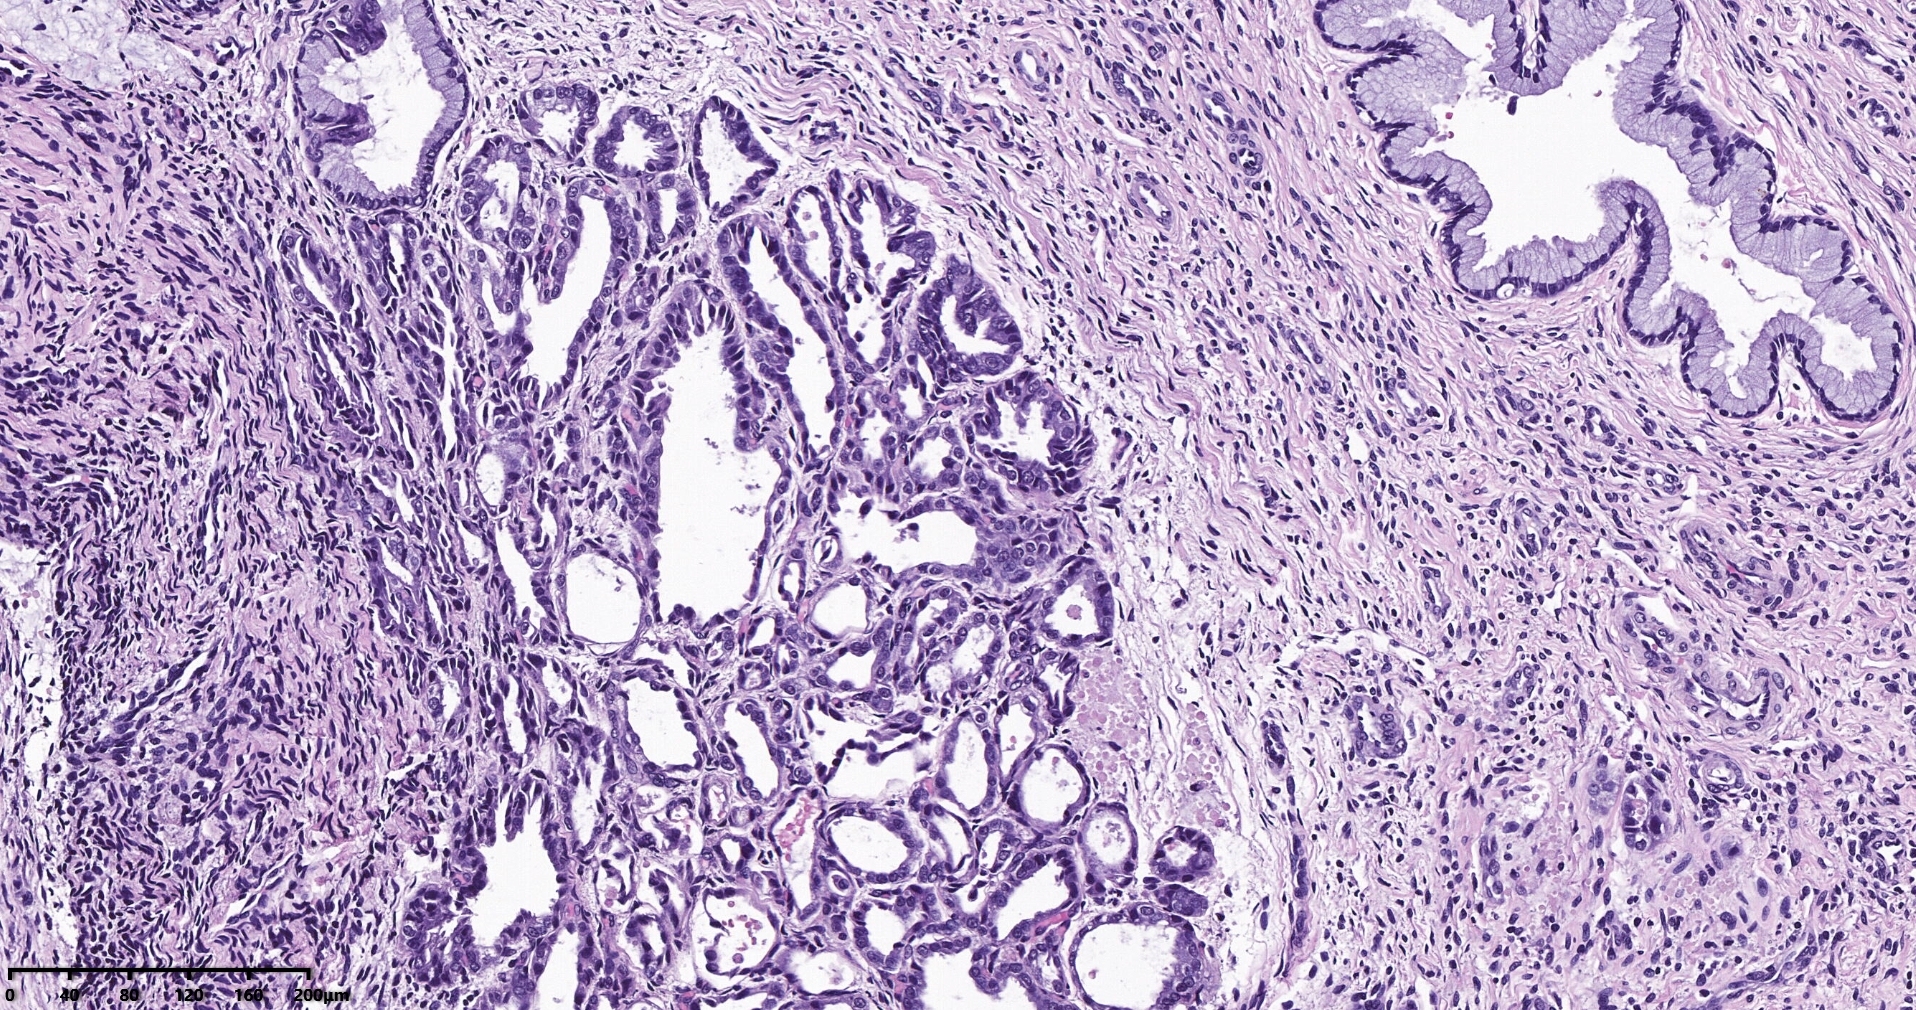

大体标本可见子宫后壁靠近宫底可见一个突出内膜面的肿物,体积约3*2*2厘米,广基,切面灰白,实性,质地脆,其余内膜略粗糙。

镜下可见肿物,腺样机构,密集,细胞异型

局部分区域腺体偏实性,细胞核大,周围胞浆空亮,会诊为子宫透明细胞癌,是不是就依据这一点?

但是其余部位内膜可见微乳头结构。

宫颈管及宫颈管可见癌组织侵犯浅层,以腺样结构为主